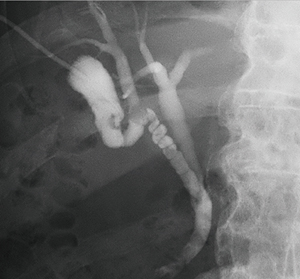

心窩部痛を訴えて近医を受診し、急性胆囊炎の疑いで当院に紹介された。腹部単純CTで胆囊管内に高吸収な結石が確認され、胆囊炎の原因と考えられたが、造影CTでは胆囊腫大に加えて、前区域の区域性胆管炎と胆管(B8)拡張が認められた。また、MRCPではB8が胆囊管に直接合流する破格が確認され、合流部に結石が存在した。PTGBDルートからの造影でも、合流部に陰影欠損像として結石が確認された(図4)。

図4 症例1:B8が胆囊管に合流する破格

合流部に結石を認める。